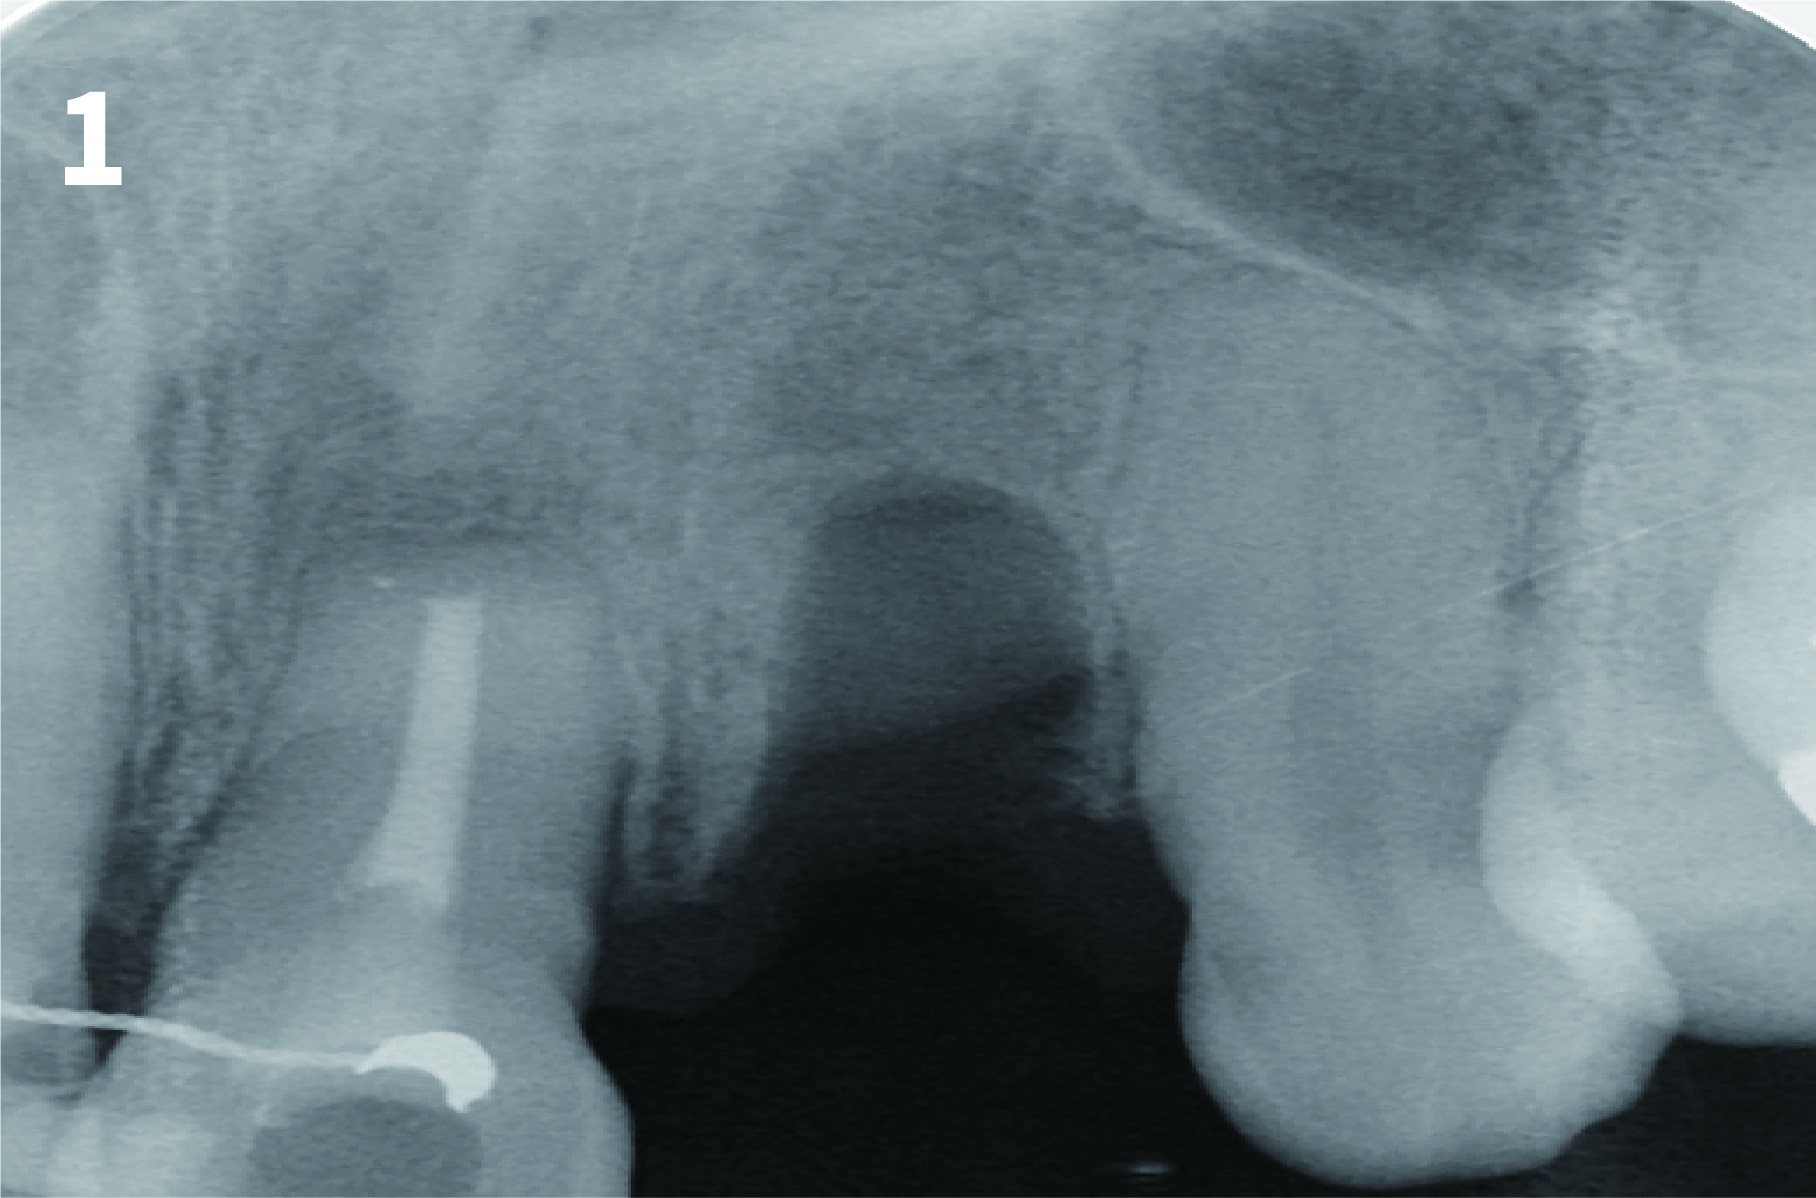

Case 1: Simply Augmented Severe Dehiscence Defect on Anterior Area